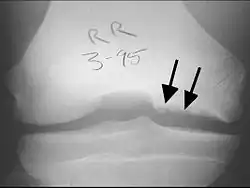

X-rays show lucency of the ossification on the anterior aspect of the knee in juvenile patients. In older people, the lesion typically appears as an area of osteosclerotic bone with a radiolucent line between the osteochondral defect and the epiphysis. The visibility of the lesion depends on its location and on the amount of knee flexion used. Harding described the lateral X-ray as a method to identify the site of an OCD lesion.[36]

Magnetic resonance imaging (MRI) is useful for staging OCD lesions, evaluating the integrity of the joint surface, and distinguishing normal variants of bone formation from OCD by showing bone and cartilage edema in the area of the irregularity. MRI provides information regarding features of the articular cartilage and bone under the cartilage, including edema, fractures, fluid interfaces, articular surface integrity, and fragment displacement.[37][38] A low T1 and high T2 signal at the fragment interface is seen in active lesions. This indicates an unstable lesion or recent microfractures.[30] While MRI and arthroscopy have a close correlation, X-ray films tend to be less inductive of similar MRI results.[38]

Computed tomography (CT) scans and Technetium-99m bone scans are also sometimes used to monitor the progress of treatment. Unlike plain radiographs (X-rays), CT scans and MRI scans can show the exact location and extent of the lesion.[39] Technetium bone scans can detect regional blood flow and the amount of osseous uptake. Both of these seem to be closely correlated to the potential for healing in the fragment.[40][41]

CT scan and projectional radiography of a case of osteochondritis dissecans of parts of the superior-medial talus.

Sagittal MRI: Linear low T1 signal at the articular surfaces of the lateral aspects of the medial condyle of the femur confirms the presence of OCD.